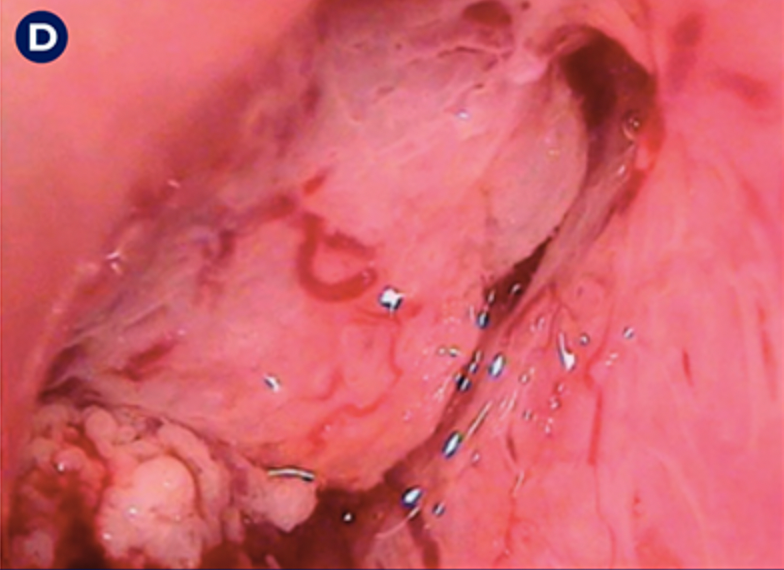

17

Q

Qual a classificação da DIP da figura?